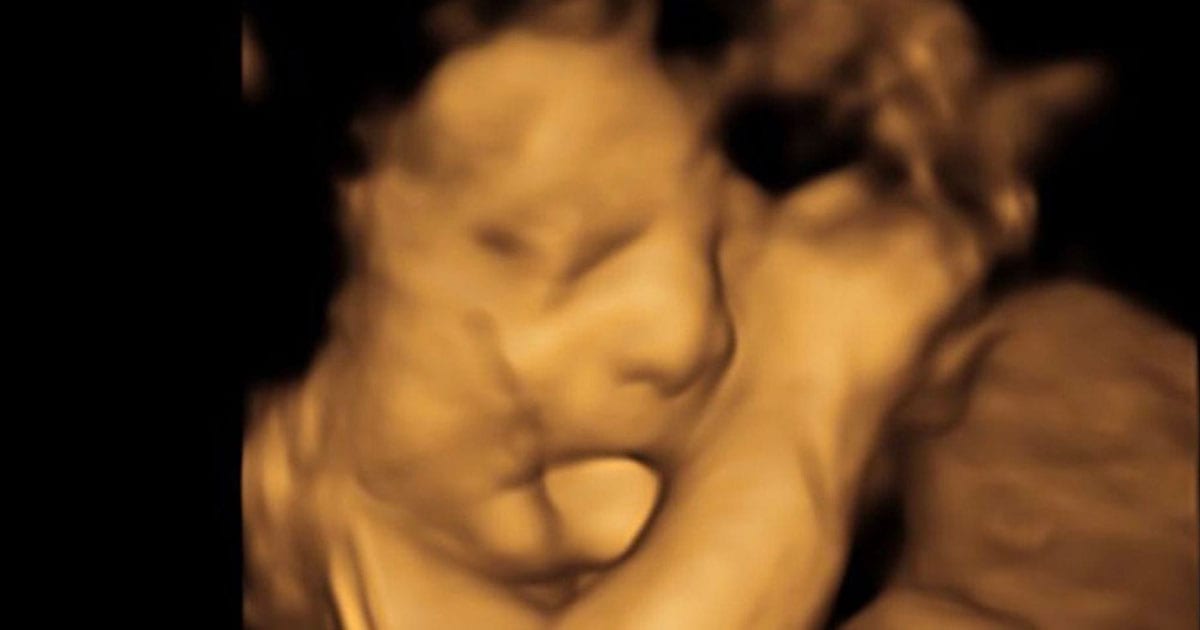

En las ecografías antes del nacimiento, los médicos pensaron que la lengua grande de Baker era “simplemente linda”.

No se dieron cuenta de que Baker podría estar lidiando con el muy raro síndrome de Beckwith-Wiedemann, que causa el crecimiento excesivo de ciertas partes del cuerpo como la lengua. La condición es extremadamente rara y solo afecta a uno de cada catorce mil nacimientos. Cuando su lengua comenzó a causar problemas respiratorios, los médicos sabían que tenían que intervenir.

Este pobre muchacho se ha quedado más en el hospital que en el hogar, y ahora los padres esperan que su lengua notablemente grande, que se estima que sea el doble de la de una lengua normal, pueda remediarse mediante cirugía. Para empeorar las cosas, a los padres de Baker se les dijo que sus marcadores tumorales habían aumentado una vez más, lo que podría ser un mal signo de que el cáncer pudiera regresar. En otras palabras, Baker aún tenía un largo camino por recorrer.